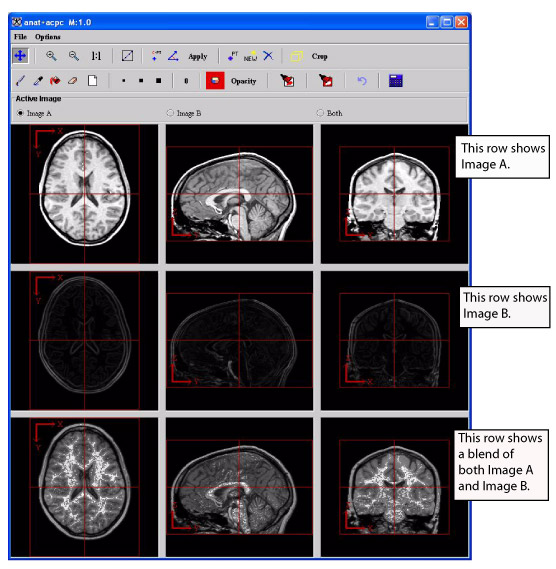

The image window for the triplanar-dual view is quite similar to the image window for the triplanar view. The File and Options menus contain the same commands except for one command-the Options menu for the triplanar view contains the command Link to Another TriImage. Since the triplanar-dual view shows two datasets in the image window and allows you to manipulate them together, linking to another image is not necessary. Most of the icons and buttons on the toolbars for both views are the same with one primary difference: The triplanar-dual view allows you to create VOIs on the images; the triplanar view does not.

Like the triplanar view, you can use the icons and buttons on the toolbar to change magnification, draw, change colors, change opacity, and apply a new intensity to selected voxels in the images.

Figure 3. Triplanar-Dual window

Image A

Performs the action only on Image A.

Image B

Performs the action only on Image B.

Both

Performs the action on both Image A and Image B.